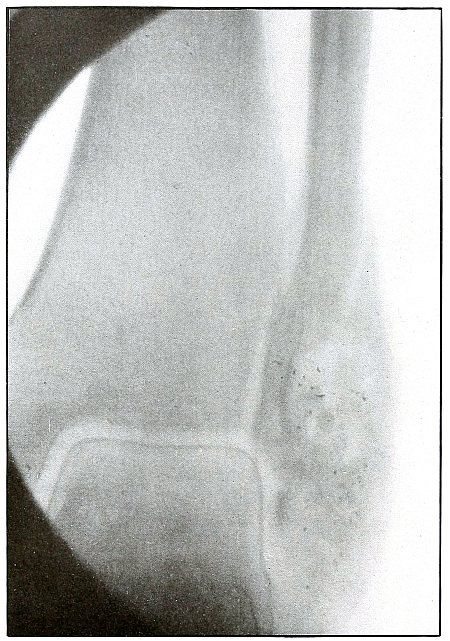

Plate 42.

_

Rifle—Plate 42.

UPPER EXTREMITY.

Gunshot Fracture of the Wrist.

This plate, presenting a lateral view of the wound shown in plate 41, shows considerable deformity of the joint, after four months’ treatment, which was even more marked two months later, when the case was discharged with an ankylosis of the wrist joint, contracture of the flexor tendons of the fingers, and slight flexor function of the thumb, permitting apposition with the first finger.

The result, while leaving much to be desired, preserved a function of the hand vastly superior to that of a forearm stump.

The treatment in such cases is always courageously conservative, with amputation only as the extreme measure to save life, with risks of judgment in favor of conservatism.

Corrective measures may be employed after management if the treatment of the infection is successful and when the case passes out of the military category. It is not possible, during a long infection, to maintain better position in such cases. [Pg 96]